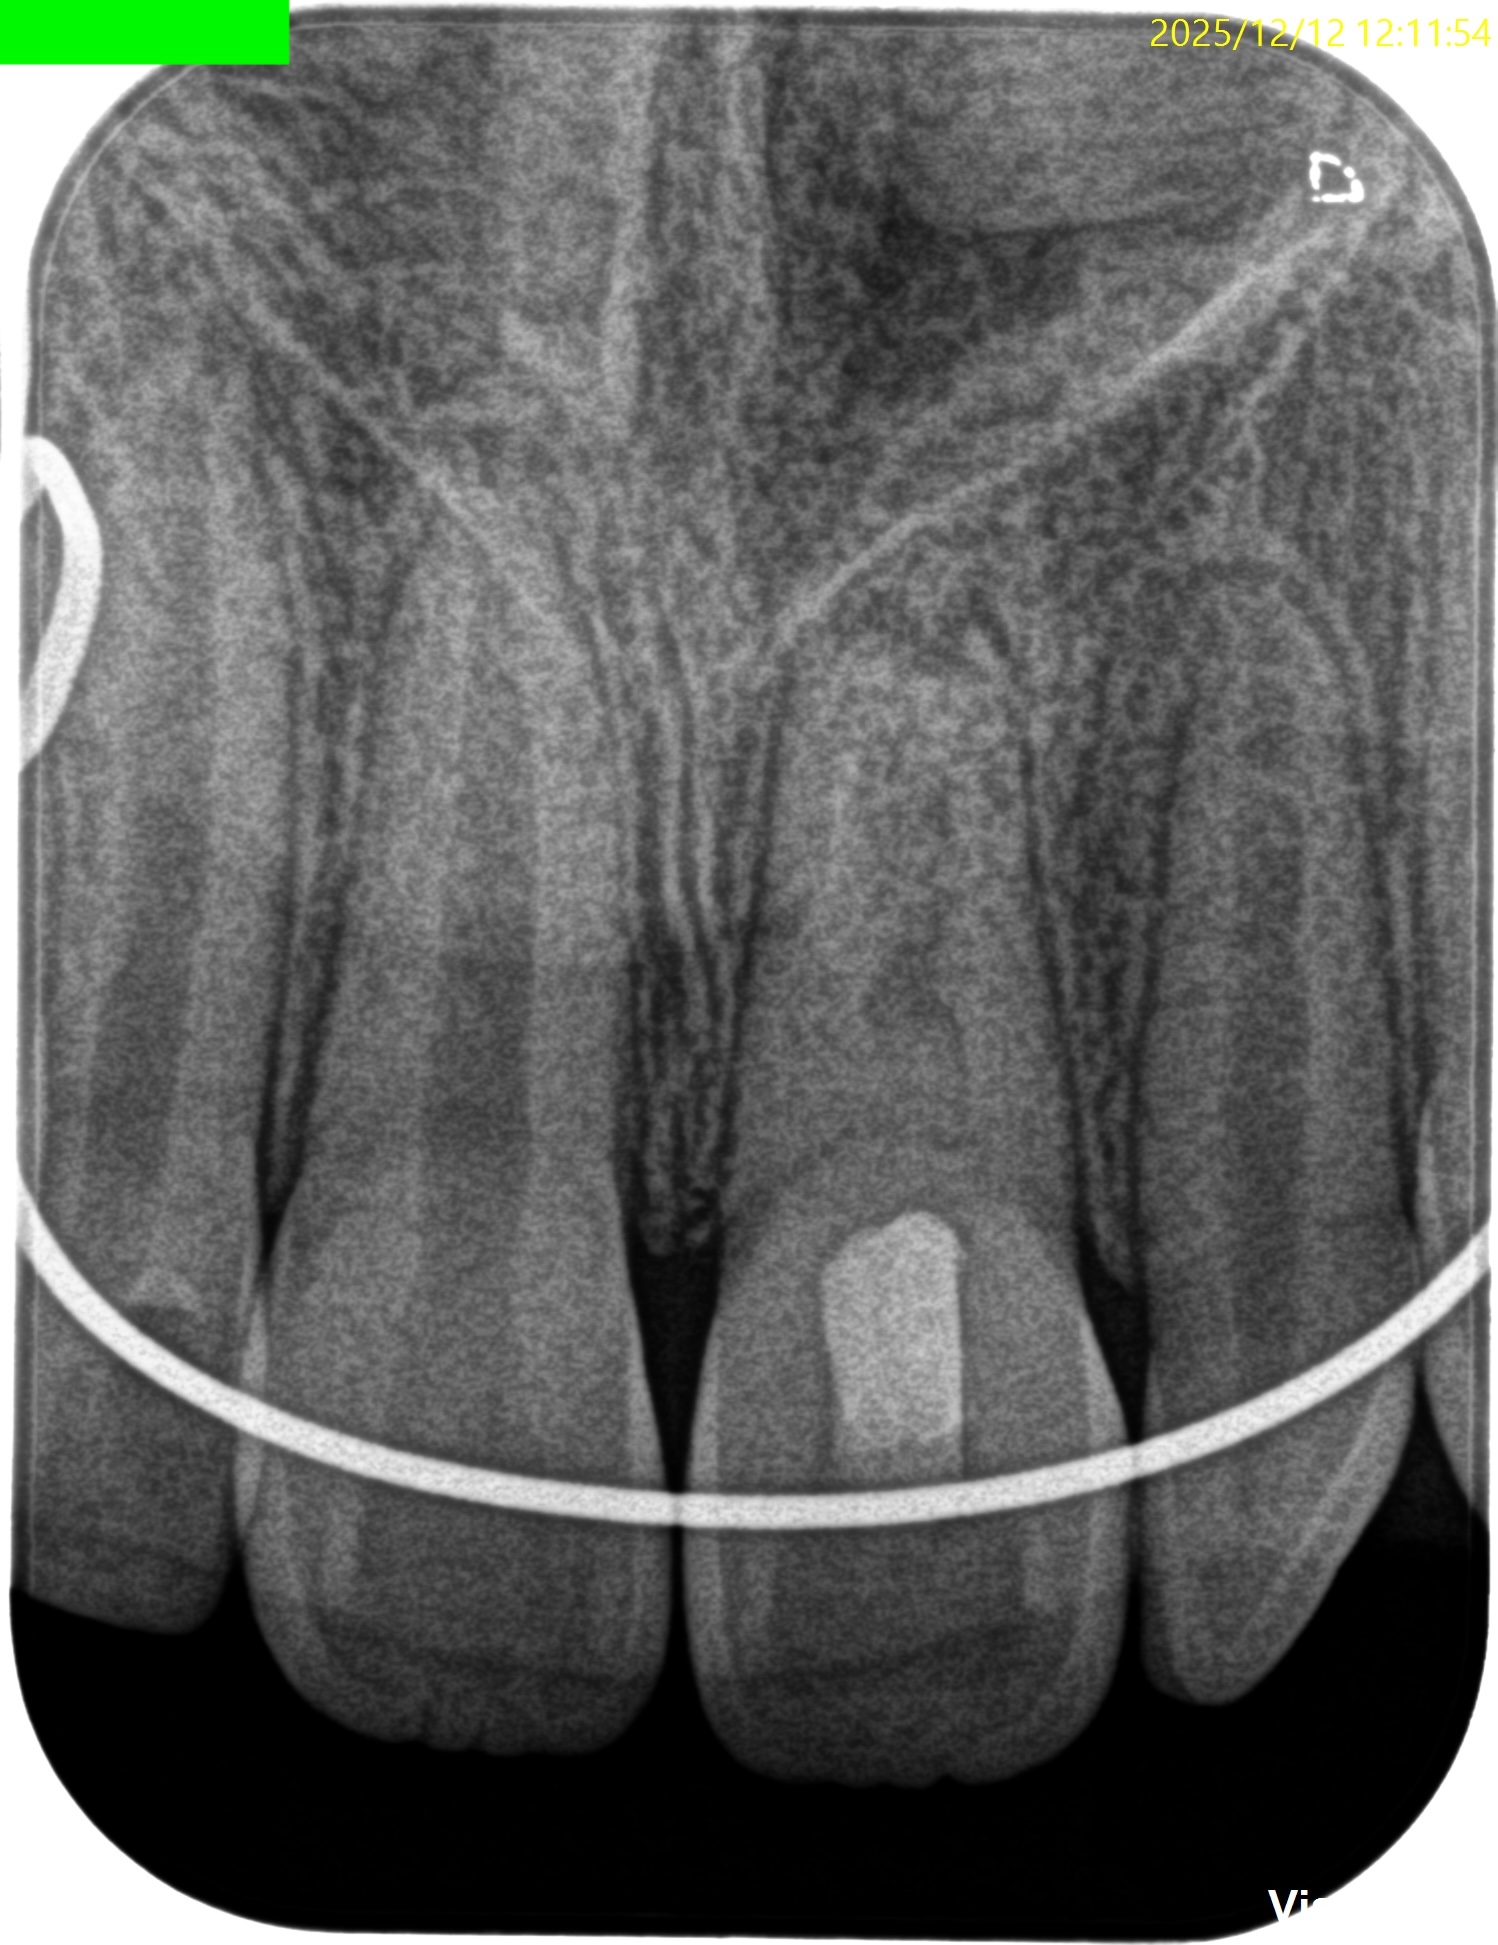

#9 Regeneration 2yr recall(2025.12.12)

初診時、1年経過観察時と比較した。

大きく問題が解決している。